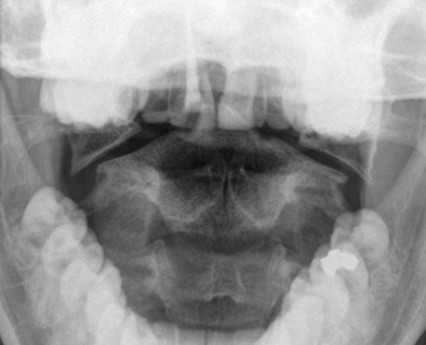

Перелом С1 Джефферсона. Рентгенография через открытый рот. С обеих сторон расширено расстояние от нижних площадок ножек С2 до боковых масс С1. Боковые массы С1 смещены латерально и перестают быть в линию с боковыми массами С1.

Перелом зуба может симулировать аномалия развития, известная как третий мыщелок.